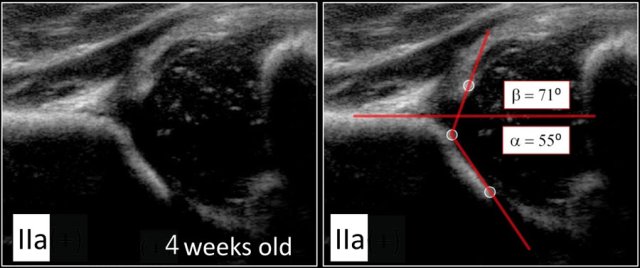

Type IIa

Here we see a hip with an alpha-angle of 55º.

The bony acetabular roof is less well-formed and there is a rounded acetabular bony rim.

The age of the child is 4 weeks, so we call this a type IIa.

About 90 % of newborns with Graf type IIa hips do not develop DDH.

The alpha-angle, which is a measurement of the bony roof of the acetabulum, mainly determines the hip type.